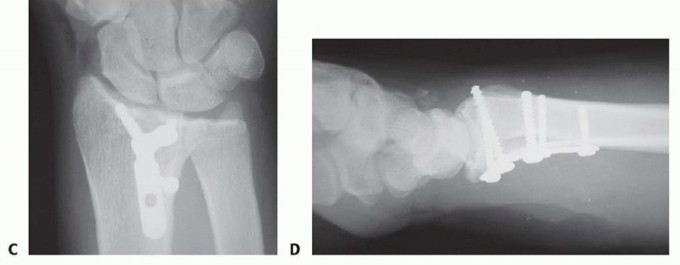

TECH FIG 5 • Volar rim fixation with small fragment plate. A,B. Shear fracture of volar rim with volar instability pattern. C,D. Fixation with small fragment plate.

TECH FIG 6 • Volar rim fixation with a volar buttress pin. A,B. Articular fracture with axial instability pattern of volar rim. C. Insertion of Kirschner wires. D. Cutting and inserting legs. E. Reduction of teardrop.(continued)

TECH FIG 6 •(continued)F. Completed fixation. G,H. Volar buttress pin fixation to control rotational alignment of volar rim fragment. Fine-tune the reduction and fix it proximally with a minimum of two screws and washers ( TECH FIG 6F-H). If needed, a blocking screw can be placed just proximal to the end of the buttress pin to prevent shortening of the fragment. Alternatively, a wire plate can be used to secure the implant proximally.

VOLAR HOOK PLATE FIXATION

TECH FIG 7 • Volar rim fixation with a volar hook plate. A. Insertion of volar hook plate over guide pin through predrilled holes. B. Completed fixation. C. Final intraoperative x-ray showing placement of two volar hook plates into separate distal rim fragments.